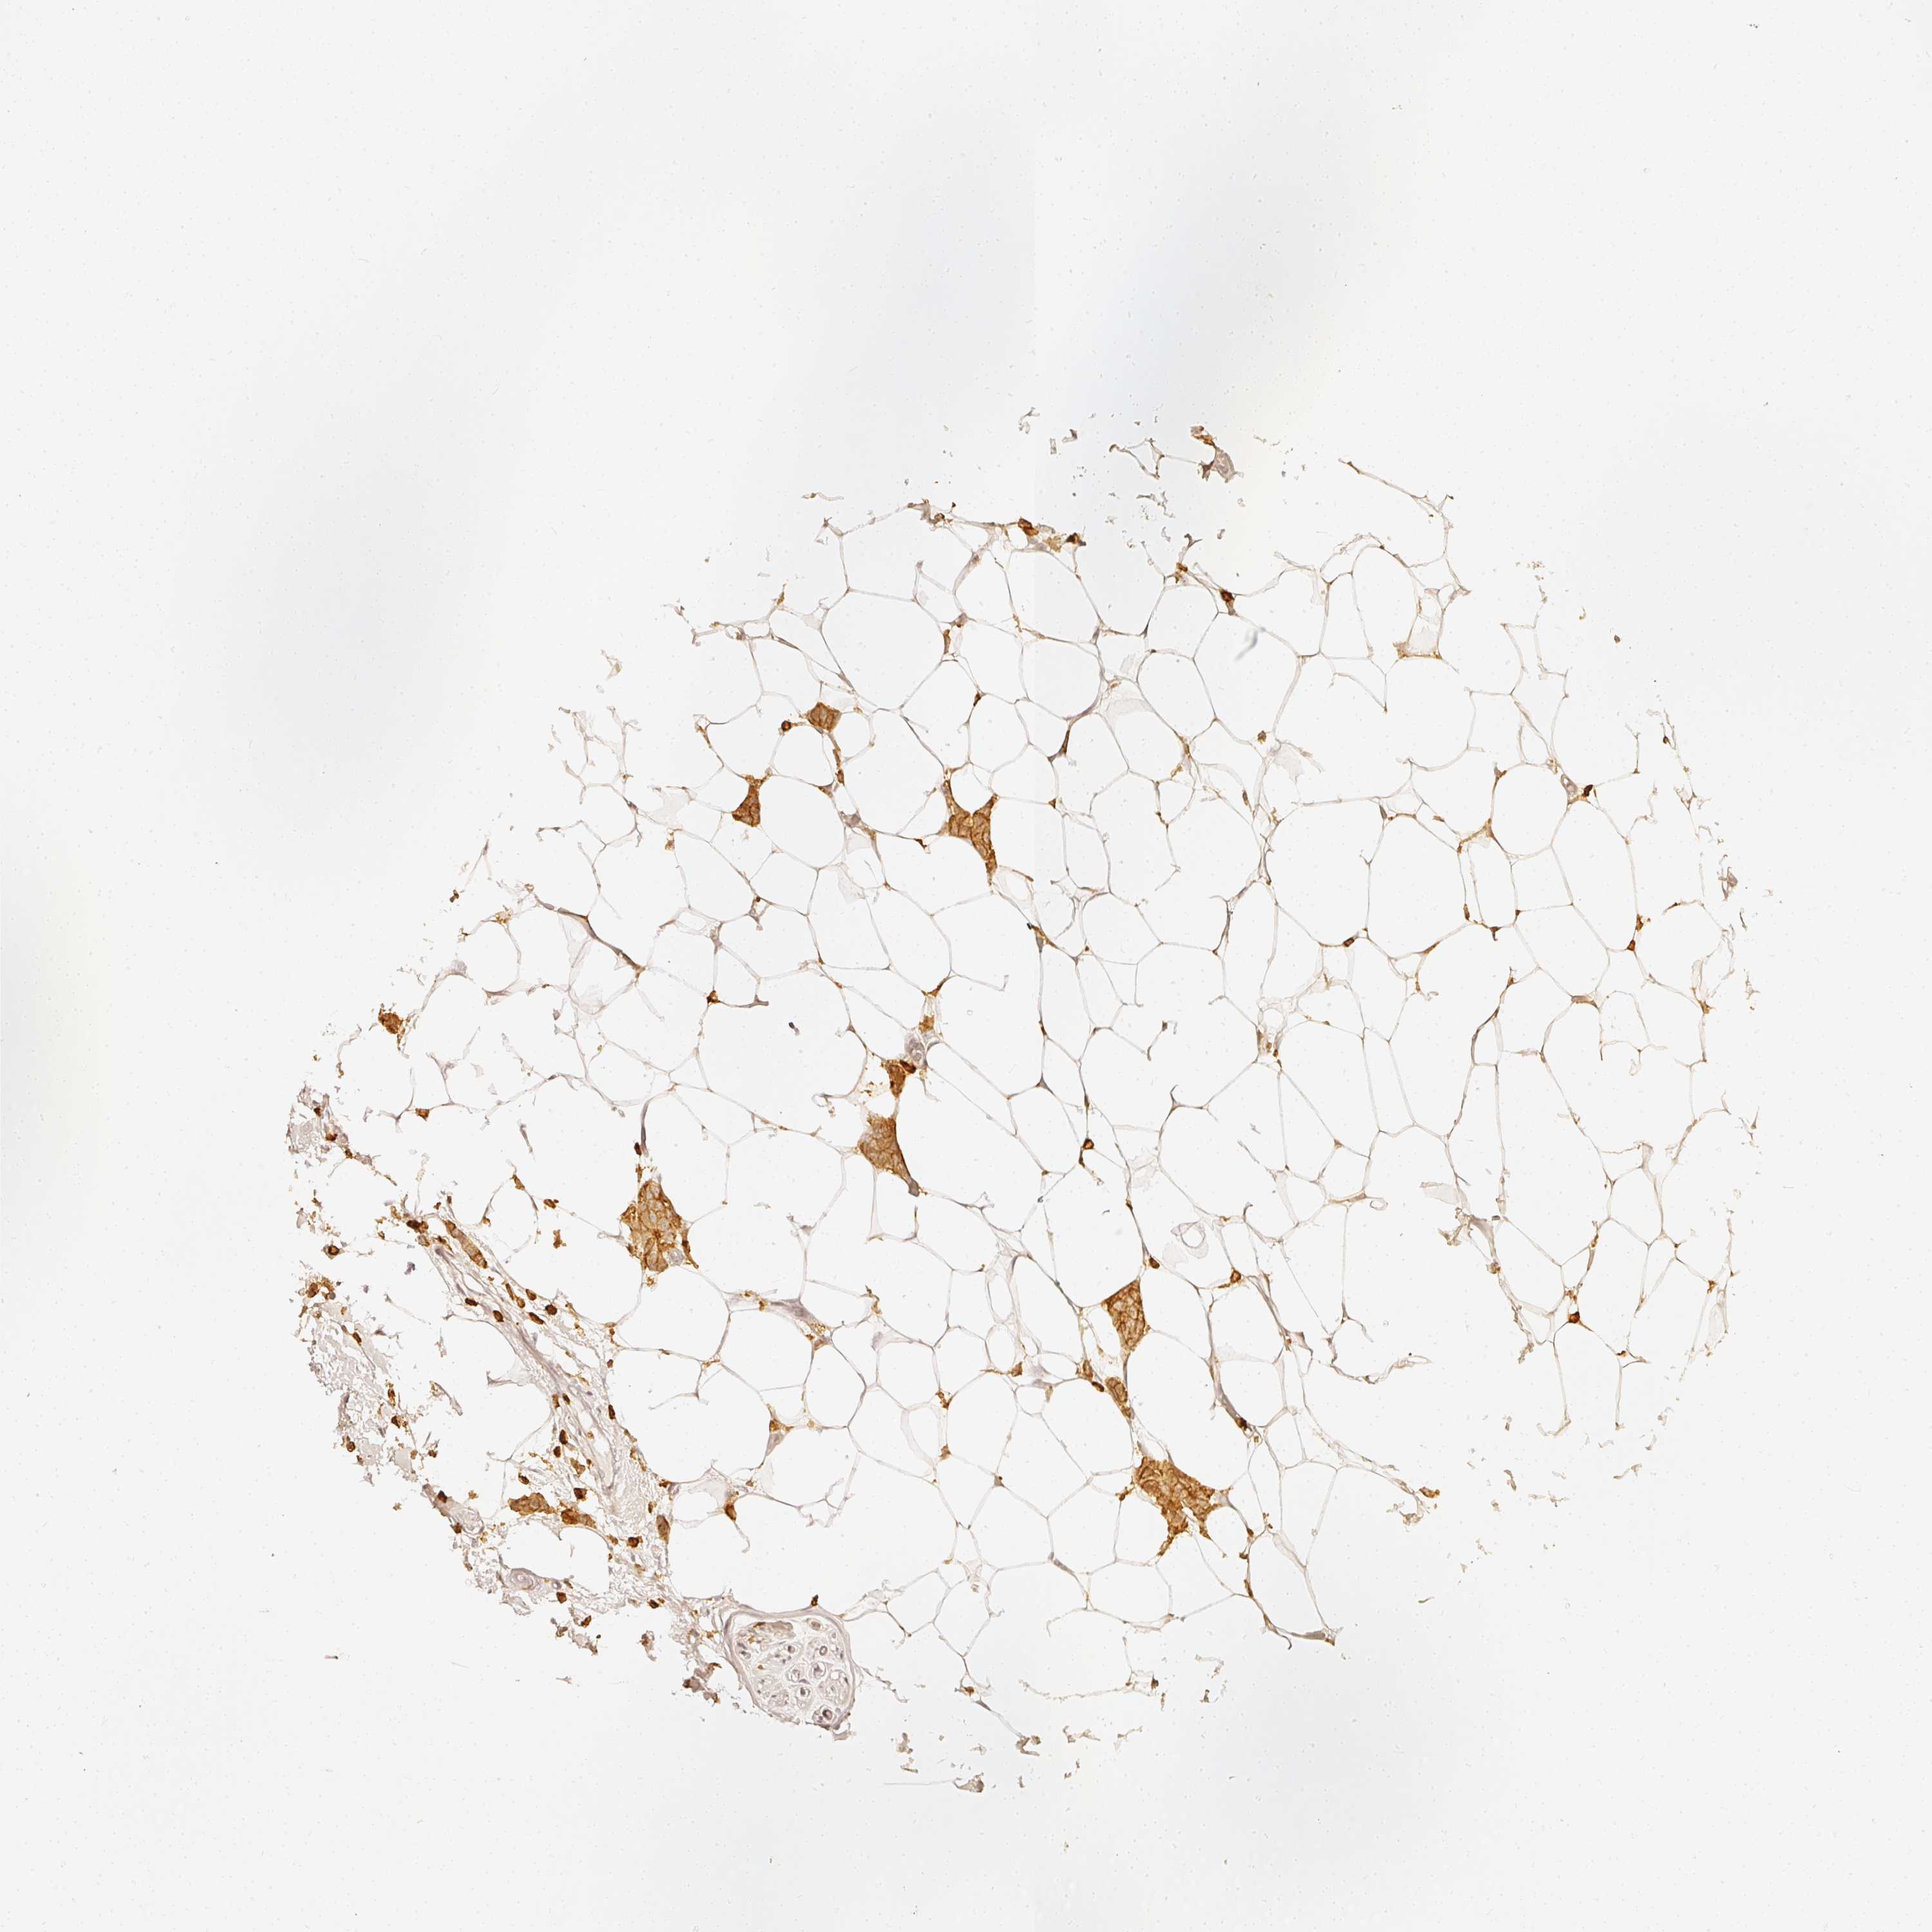

CANCER BREAST CANCER Show tissue menu

BRCA TCGA BRCA VALIDATION PROTEIN EXPRESSION

ANTIBODIES

AND

VALIDATION